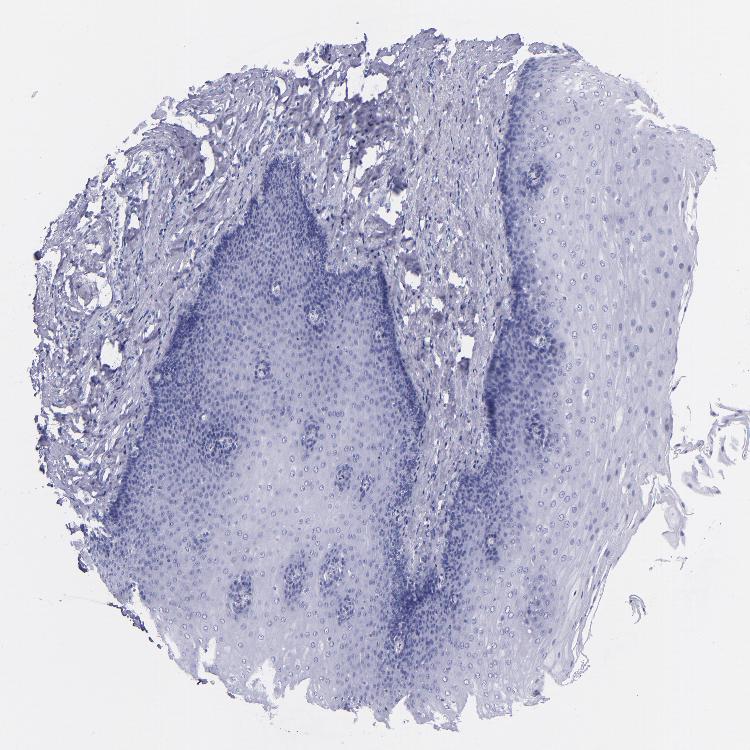

ESOPHAGUS - Antibody stainingi

Antibody staining in the annotated cell types in the current human tissue is reported as not detected, low, medium, or high, based on conventional immunohistochemistry profiling in selected tissues. This score is based on the combination of the staining intensity and fraction of stained cells.

Each image is clickable and will lead to virtual microscopy that enables deeper exploration of all samples and also displays staining intensity scores, fraction scores and subcellular localization as well as patient and tissue information for each sample.

Antibody HPA007863Antibody CAB002226

Squamous epithelial cells Not detectedNot detected